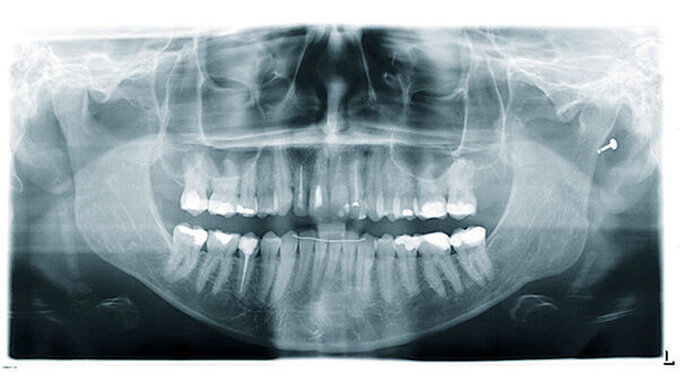

Der klinische Verlauf von externen Oberflächenresorptionen ist in der Regel asymptomatisch und die betroffenen Zähne reagieren meist positiv auf Sensibilitätstests. Die radiologischen Befunde sind in Form und Größe sehr heterogen (Abbildung 5). Im Zusammenhang mit kieferorthopädisch bedingten Resorptionen ist beispielsweise häufig eine scheinbare Abstumpfung der Wurzelspitze zu beobachten, wodurch die Zähne insgesamt kürzer erscheinen als die nicht von resorptiven Prozessen betroffenen Nachbarzähne [Sameshima und Iglesias-Linares, 2021; Sondeijker et al., 2019].

Entzündliche Resorptionen sind bei fehlender klinischer Symptomatik häufig ein radiologischer Zufallsbefund. Sie können aber auch mit einer symptomatischen Entwicklung wie irreversibler Pulpitis oder apikaler Parodontitis einhergehen. Resorptionsdefekte an der Wurzeloberfläche erscheinen im Röntgenbild aufgrund ihres raschen Fortschreitens oft zerklüftet (Abbildung 6). Entlang einer unregelmäßigen Wurzelaußenkontur sind transluzente Zonen im Sinne von „schüsselförmigen“ Resorptionslakunen unterschiedlicher Größe zu erkennen. Häufig findet man verkürzte Wurzeln mit zusätzlichen periapikalen Aufhellungen. In fortgeschrittenen Fällen kann die Resorption bis ins Zahninnere vordringen und den Wurzelkanal perforieren [Andreasen und Hjørting-Hansen, 1966; Finucane und Kinirons, 2003].

Dabei wird das Dentin zunehmend durch Odontoklasten abgebaut und durch Knochengewebe ersetzt [Andreasen, 1980; Souza et al., 2020]. Die daraus resultierende Verschmelzung von Zahn und Alveolarknochen wird als Ankylose bezeichnet und äußert sich klinisch durch ein helles, metallisches Klopfgeräusch und das Fehlen der physiologischen Zahnbeweglichkeit (Abbildung 8). Im Laufe der Gebissentwicklung kann es als Folge der Ankylose zu Infrapositionen der betroffenen Zähne kommen. Der Parodontalspalt ist röntgenologisch nicht mehr eindeutig erkennbar [Andersson et al., 1984].